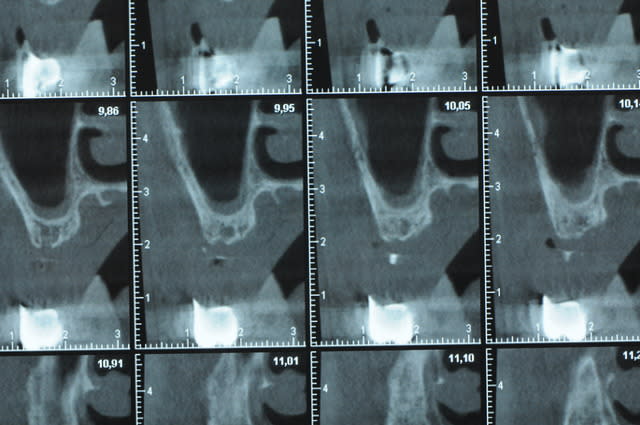

Une petite étude de ton cas D57

Sous réserves bien sur de voir l’animal en vrai

Les zones exploitables radiologiquement parlant:

Coupes implant

2,3 40100

4,96 35130 avec sinus lift mais difficile

5,25 35150

6,02 35130

6,78 35115 après réduction de hauteur de crête

7,26 35115 après réduction de hauteur de crête

8,51 35150

10,43 40115 ou 50115

11,10 40115

Ce qui nous fait 9 implants possible évidement avec un comblement de sinus on augmenterait encore les zones implantable mais ce n’est pas le but recherché, avec 8 (4+4) il doit être possible de faire une belle barre support de complet

Je n’ai pas eu le temps de te téléphoner, ça viendra